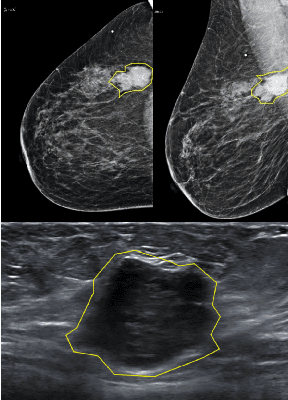

Abstract:Mammography and ultrasound are extensively used by radiologists as complementary modalities to achieve better performance in breast cancer diagnosis. However, existing computer-aided diagnosis (CAD) systems for the breast are generally based on a single modality. In this work, we propose a deep-learning based method for classifying breast cancer lesions from their respective mammography and ultrasound images. We present various approaches and show a consistent improvement in performance when utilizing both modalities. The proposed approach is based on a GoogleNet architecture, fine-tuned for our data in two training steps. First, a distinct neural network is trained separately for each modality, generating high-level features. Then, the aggregated features originating from each modality are used to train a multimodal network to provide the final classification. In quantitative experiments, the proposed approach achieves an AUC of 0.94, outperforming state-of-the-art models trained over a single modality. Moreover, it performs similarly to an average radiologist, surpassing two out of four radiologists participating in a reader study. The promising results suggest that the proposed method may become a valuable decision support tool for breast radiologists.